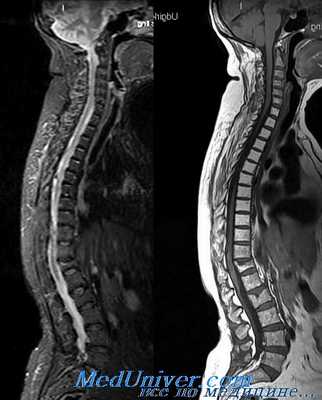

Срочное выполнение МРТ показано всем пациентам с неврологическим дефицитом, несогласующимися уровнями скелетной и неврологической травмы и прогрессированием неврологических расстройств. Несмотря на отрицательные результаты обзорных снимков, МРТ может оказаться незаменимой для определения повреждений задних связочных структур. Тем не менее, МРТ не относится к рутинным методам при политравме, так как эти пациенты часто нуждаются в применении вспомогательных устройств (дыхательная аппаратура, шины для иммобилизации конечностей, помпы для внутривенных инфузий), которые могут повлиять на магнитное поле.

Магнитно-резонансная томография наиболее информативна для оценки состояния мягкотканных структур. Она применяется для обнаружения травм, злокачественных и доброкачественных опухолей. По результатам МРТ можно выявить воспалительные или деструктивно-дегенеративные процессы, протекающие в шейном отделе позвоночника. Исследование проводится для диагностирования сужения позвоночного канала, деформации позвонков и изменений околопозвоночных тканей, определения участков спинного мозга с ухудшенным кровоснабжением.